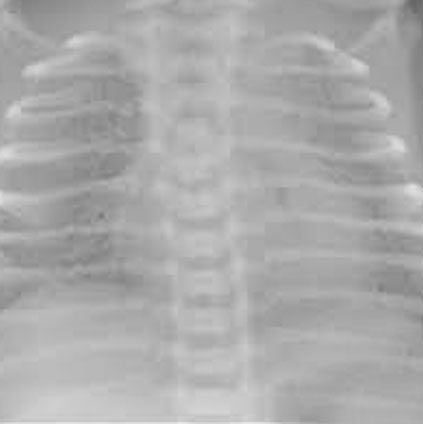

Chest X-ray showing hyaline membrane disease (HMD) with underdeveloped lungs in a premature newborn